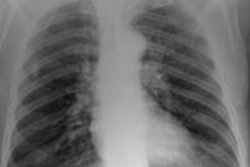

The study aimed to compare image quality, radiation dose, and laboratory time between chest radiography and ultralow-dose chest CT reconstructed with advanced adaptive iterative dose reduction (AIDR 3D, Toshiba Medical Systems).

Aaløkken and colleagues examined 13 patients with suspected pulmonary lesions, following chest radiography with ultralow-dose CT acquired on a 320-detector-row scanner (Aquilion One, Toshiba). Images were acquired at 135 mA and 10 kV, with 0.5-mm slice thickness and rotation time of 350 msec.

Three experienced chest radiologists rated both sets of images for pathological findings on a three-point scale, and image quality was rated according to nine criteria of the European guidelines for chest CT and chest radiographs.

"Both image quality and the ability to detect and exclude pathology was strikingly better for ultralow-dose CT than for radiography," although laboratory time was slightly longer for CT, and CT dose was higher but still minimal, Aaløkken said.

The study demonstrated "superior image quality for CT versus radiography," he said. "The similar radiation dose and laboratory time leaves cost as the only reasonable argument in favor of radiography." Otherwise, "it means we can say goodbye to radiography."